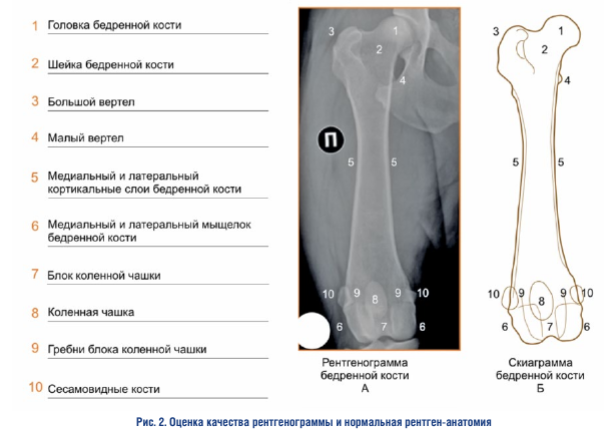

Оценка ортопедической проекции — дистальный эпифиз. При интерпретации правильной ориентации дистального эпифиза бедренной кости во фронтальной плоскости необходимо учитывать усредненную совокупность признаков, каждый из которых по отдельности не является абсолютным критерием адекватности проекции (рис. 3)

Положение сесамовидных костей. Сесамовид- ные кости должны быть разделены кортикальными слоями пополам. Сесамовидные кости являются структурой, которая относится к бедренной кости, но не принадлежит ей, поэтому, например, при изменении формы сесамовидных костей, при наличии остеоартрита сезамо-бедренных суставов, данный критерий может не отражать истинного положения дистального эпифиза бедренной кости.

Положение межмыщелковой ямки и контуров мыщелков. Межмыщелковая ямка должна иметь форму равномерно вогнутой окружности. Контуры латерального и медиального мыщелков должны хорошо визуализироваться, быть прямыми и располагаться посередине относительно ширины дистального эпифиза.

Положение коленной чашки. Коленная чашка должна находиться в своем нейтральном положении относительно блока коленной чашки на линии, соединяющей сесамовидные кости, и делить коленную чашку на примерно равные верхнюю и нижнюю части. Такая ориентация коленной чашки свидетельствует о параллельном положения бедренной кости относительно рентгеновской кассеты (фронтальной плоскости).

В тех случаях, когда выполняется рентгенография бедренной кости пациенту, у которого присутствует не вправляемый латеральный или медиальный вывих коленной чашки, и она располагается за пределами своего блока, необходимо ориентироваться только на линию, проведенную между сесамовидными костями.

Оценка ортопедической проекции — проксимальный эпифиз. При интерпретации правильной ориентации проксимального эпифиза бедренной кости во фронтальной плоскости необходимо учитывать усредненную совокупность признаков, каждый из которых по отдельности не является абсолютным критерием адекватности проекции 1.

Положение малого вертела. Малый вертел должен хорошо визуализироваться, иметь четкие контуры и точные границы, его медиальный край должен уверенно, но не избыточно выступать за границы медиального кортикального слоя бедренной кости.

Визуализация большого вертела. Большой вертел должен хорошо визуализироваться, иметь четкие контуры и точные границы.

Визуализация шейки и головки. Головка и шейка должны хорошо визуализироваться, иметь четкие контуры и точные границы.

При наличии выраженного остеоартрита тазобедренного сустава границы шейки и головки бедренной кости могут быть значительно изменены, что может затруднять нормальное определение их контуров и точных границ.